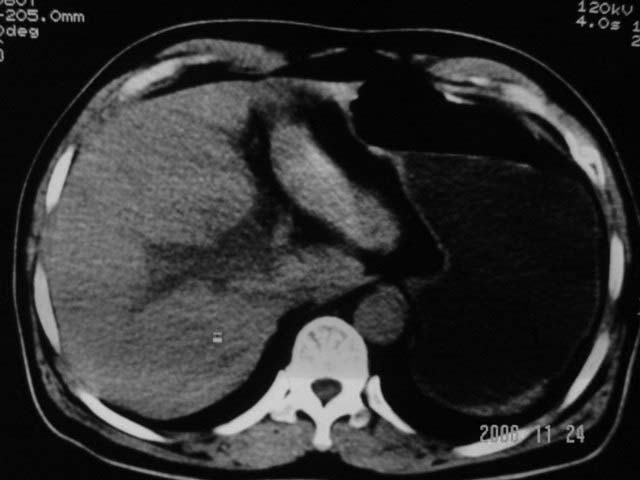

劳烦各位老师看一下最后一幅箭头指的地方是不是胆总管结石.ct值约63hu.

胆总管内结节状高密度灶,边缘隐约可见低密度环绕,首先考虑结石伴肝内胆管扩张; 2、胆囊增大,胆囊炎

1.肝内外胆管扩张,楼主箭头所示处多系结石.

楼主的箭头标的太棒了,不看最后一副图,我都没看到胆管下端有问题,象结石